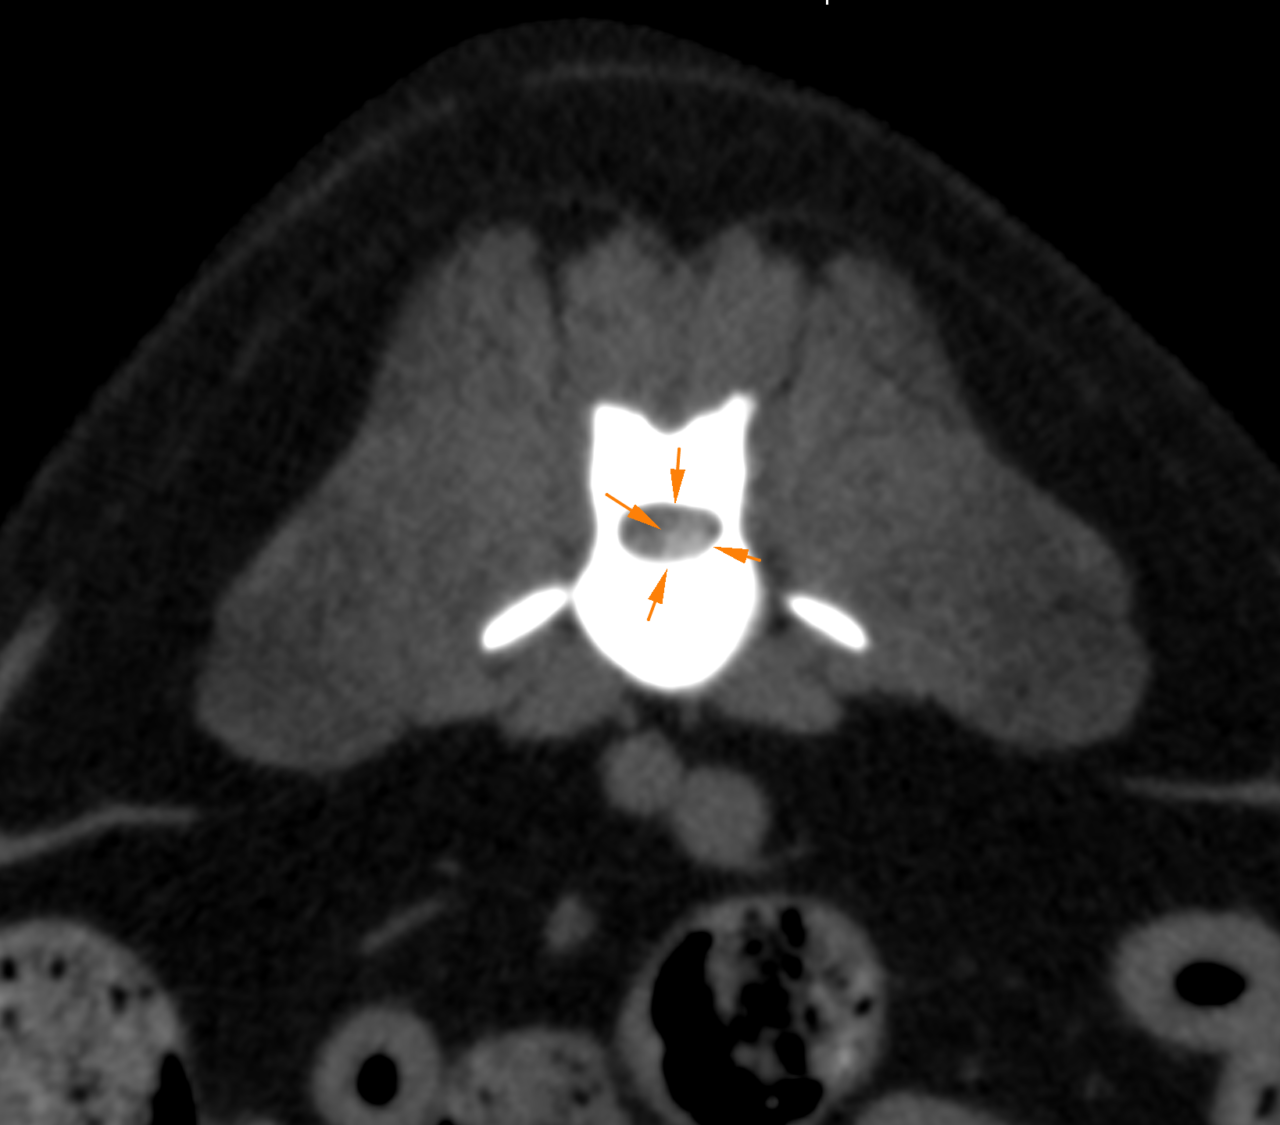

中年齢のミニチュア・ダックスさんがG1の椎間板ヘルニアを内科的に管理していたが、急に症状が悪化、腰の痛みと起立出来なくなったとの事で来院されました。幸いにも深部痛覚は保たれていました。Laminectomyで脊柱管内に侵入すると静脈洞から顕著に出血が確認されました。椎間板物質の摘除と共に脊髄の除圧を行いました。5日後には随意運動が回復し、7日で退院となりました。内科的な管理を行う場合は厳格なケージレストが行えないと、一気に神経症状が悪化することがあります。